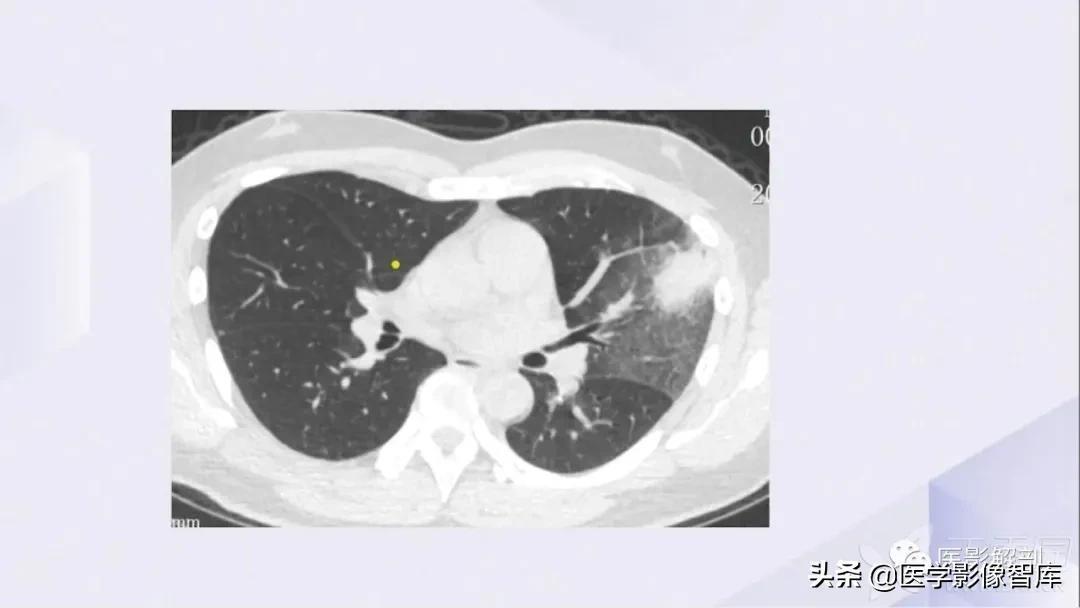

肺部CT解剖(高清图谱)